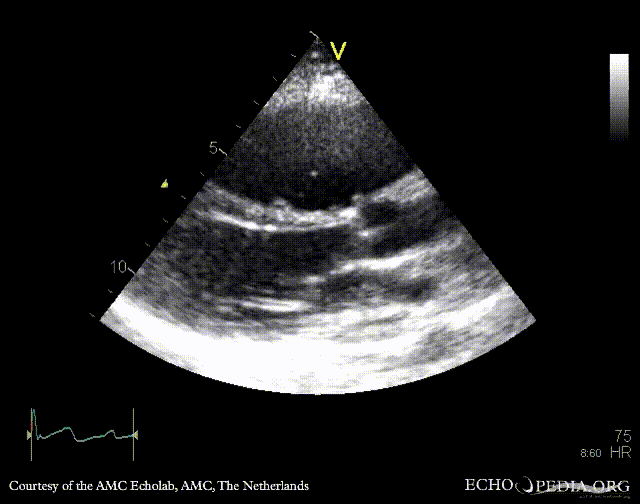

A4CH: Color Doppler, severe tricuspid regurgitation Continuous-wave signal of severe tricuspid regurgitation, pulmonary hypertension